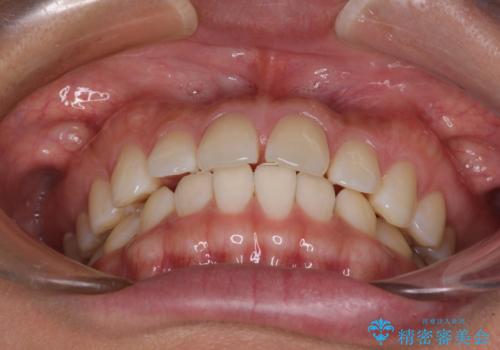

【モニター】前歯のすきっ歯をインビザラインで改善

- 上顎前歯の隙間と口元の突出感を気にして来院された患者様です。

高校生の時に行った矯正治療の後戻りであり、歯列不正は軽度であったので、インビザラインにて治療を行うこととしました。